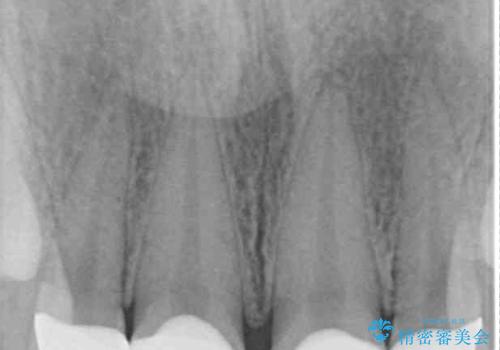

- 前歯の矮小歯と捻れや変色を気にして来院された患者様です。

結婚式が近いということもあり、前歯4本をオールセラミッククラウンにて補綴治療することとしました。

前歯の捻れは、オールセラミッククラウンよりも矯正治療による改善の方が、歯を削らなくて済むためお勧めとなります。

しかし、矮小歯の改善はオールセラミッククラウンでの補綴治療が必要であり、幅径のバランスを取る必要があるため、4前歯の補綴治療を選択しました。